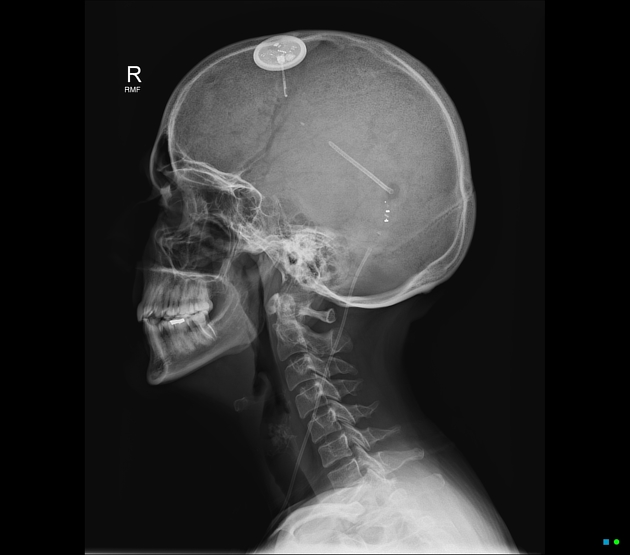

Posterior VP shunt in situ. A more anterior wireless ICP monitor is also present. - Brain herniations (supratentorial, uncal, infratentorial)